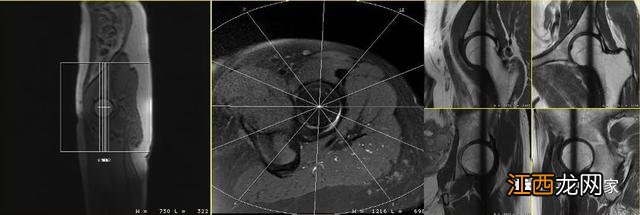

不压脂的PDWI序列可以将高信号的骨髓和低信号的盂唇清晰分开,可以更好的评估髋臼、股骨近端骨质、髋臼过度覆盖以及髋臼发育不良等 。

文章插图

放射状髋臼盂唇扫描所得的髋骨图像会产生放射状的交叉伪影,其为诊断提供的信息是有限的,且所得的图像对读片者要求较高,目前该序列不作为常规的扫描序列 。